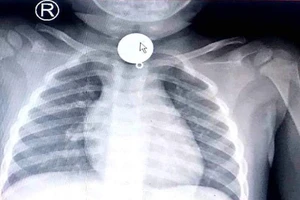

Trẻ tắc ống thực quản vì nuốt mặt dây chuyền